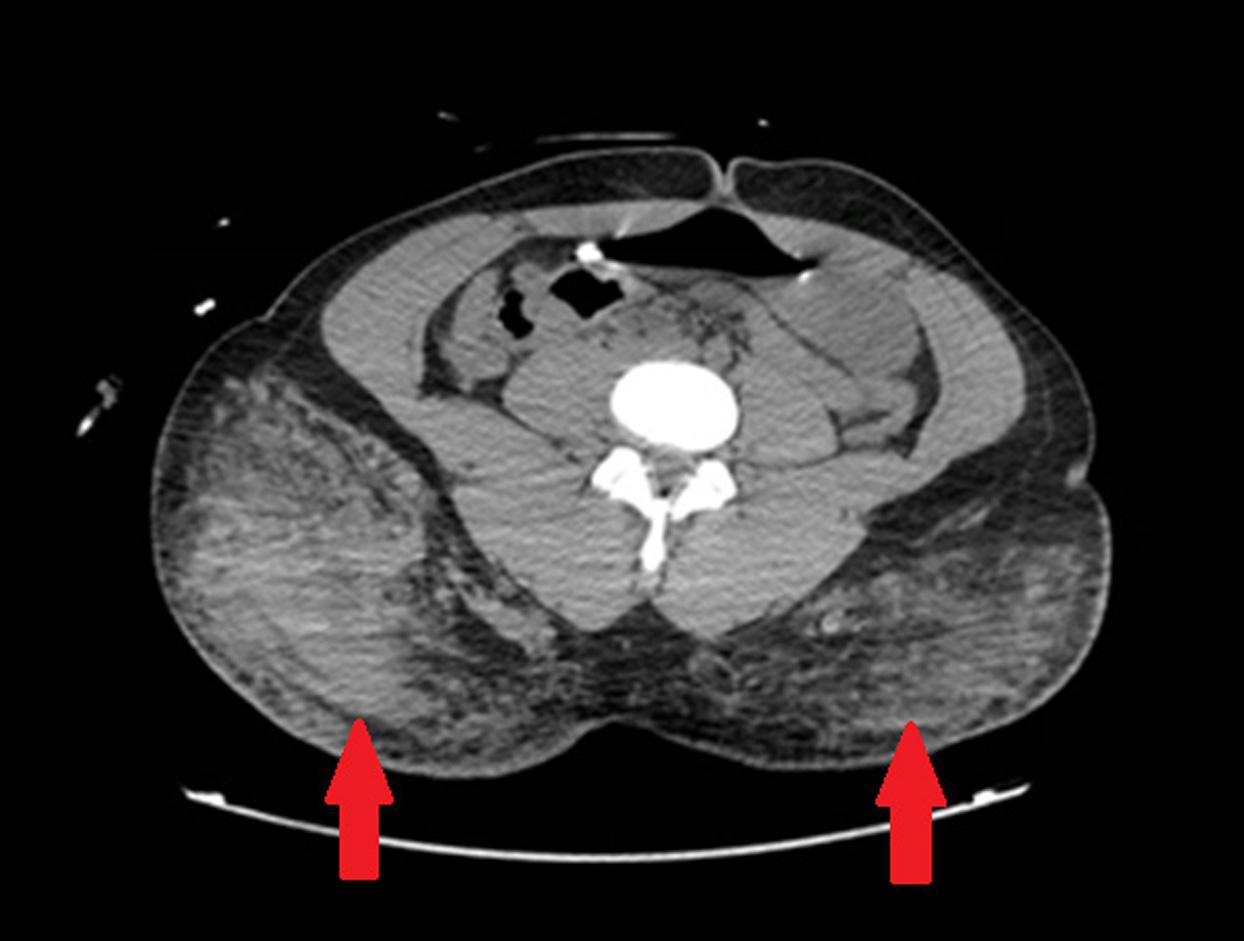

155 Transcatheter Arterial Embolization for Atraumatic Splenic Rupture in TEE-negative Endocarditis: A Case Report

Daniel P. High, Jose M. Acosta-Rullan, Danay Herrera, Mauricio Danckers, Daniel Heller, Daniel Zapata